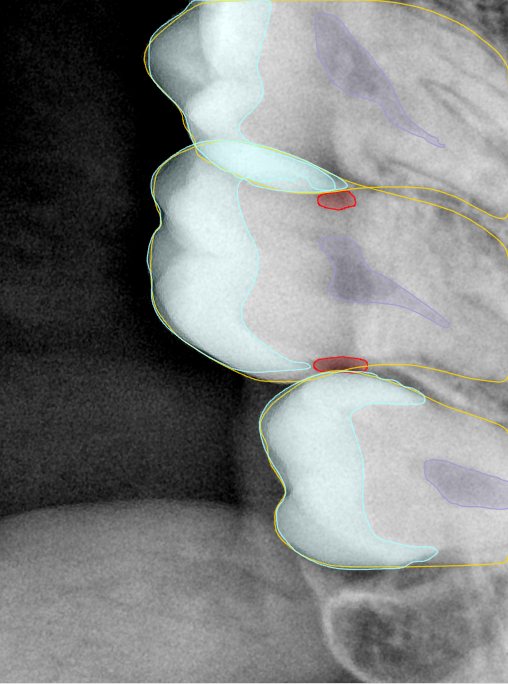

CR/DR 牙齿分割阶段记录

当前进展

- 完成了 CR/DR 牙齿相关分割训练

- 当前结果已经达到阶段预期,但仍有细节问题需要继续处理

相关测试

遇到的问题

- 训练过程中出现过 mask 下移问题

- 部分结果会出现 box 填充异常

- mask 边缘仍然有比较明显的锯齿感

参考

第二版算法问题测试

Updated: 2026-04-13(更新日期)

| 第一版 | 第二版 | 是否解决 | |

|---|---|---|---|

![]() | ![]() ![]() 边角识别有问题 龋齿识别不全 牙髓识别不全 | ![]() | 解决 |

![]() | ![]() 边角识别有问题 识别信息有误 自查(牙冠识别不全) | ![]() | 解决 |

![]() | ![]() ![]() 边角识别有误 大范围填充识别遗漏 | ![]() | 解决 |

![]() | ![]() 识别信息不全 | ![]() | 解决 |

![]() | ![]() ![]() 边角问题 牙胶识别不全 牙冠识别不全 | ![]() | 解决 |

![]() 换图片 | ![]() | ![]() 牙冠部分稍微白了一些就识别成小范围修补,部分判断异常 | 部分解决,修复类略敏感,牙冠部分稍微白了一些就识别成小范围修补,部分判断异常。 |

![]() | ![]() ![]() 牙冠识别不全 牙髓不全 根尖炎龋齿识别有误 | ![]() | 解决 |

![]() | ![]() | ![]() | 解决 |

![]() 换图片 | ![]() | ![]() | 解决 |

![]() | ![]() 牙冠识别有误 | ![]() | 解决 |

![]() 换图片 | ![]() ![]() 边角识别有误 | ![]() 修复类敏感 | 部分解决,图像过白,导致修复类判断异常。 |

![]() 换图片 | ![]() 牙冠识别不全 | ![]() 修复类敏感 | 部分解决,图像过白,导致修复类判断异常 |

结论:修复类出现了不鲁棒的情况,后续需要加入轮廓的扩充数据进行增强。